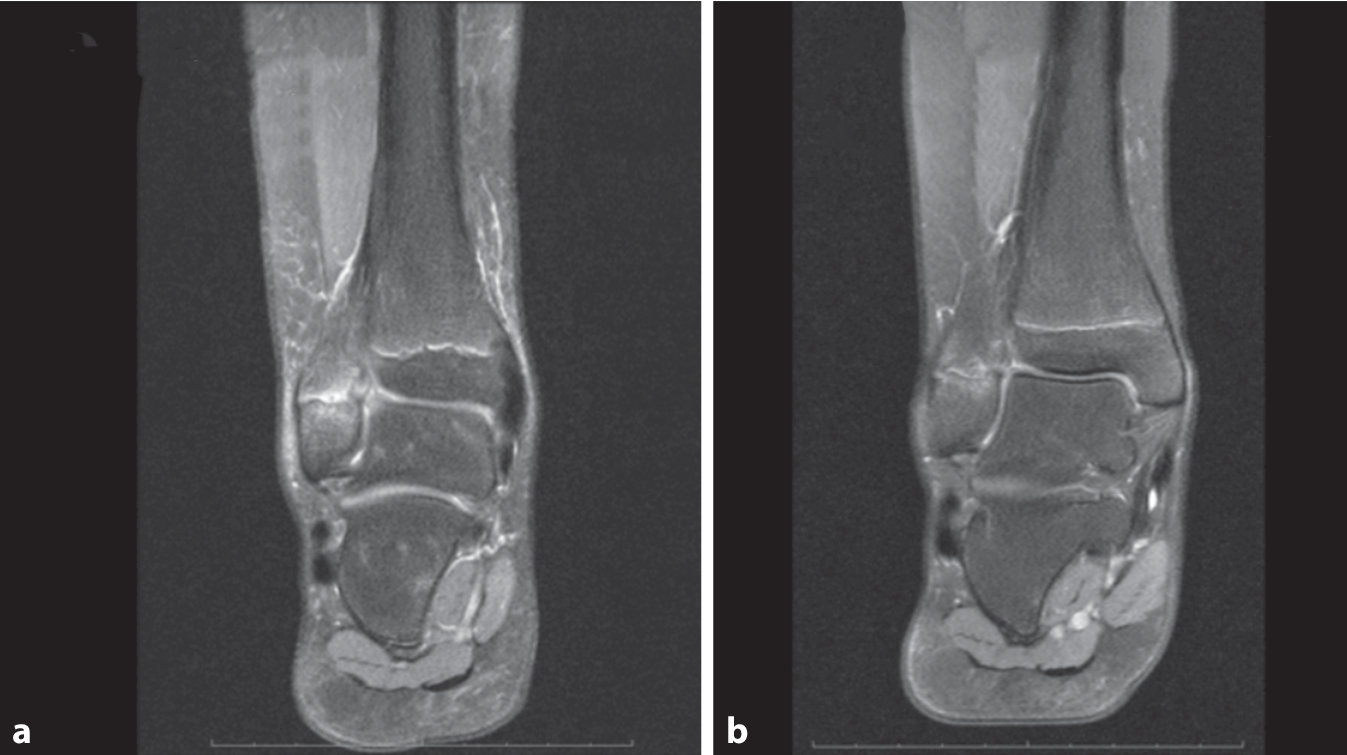

Ein nachtteiliger Effekt auf offene Wachstumsfugen wird seit mehr als 2 Dekaden diskutiert, basierend auf einer einzigen hochenergetischen Studie bei Ratten [15]. Seinerzeit wurden bei 20 kV 1500 Schüsse auf die Wachstumsfuge fokussiert, wobei bei 33 % der Tiere ein vorzeitiger Fugenschluss beobachtet wurde. In anderen Modellen konnte dieser Effekt nicht repliziert werden, so beispielsweise bei 18 Hasen (0,32 mJ/mm2 800 Schuss; [16]), wobei die Harmlosigkeit auch in einer weiteren Untersuchung bestätigt werden konnte [17]. Auch klinisch ist weder bei der Behandlung des M. Osgood-Schlatter [18] des Heranwachsenden noch bei Apophysenverletzungen [19] ein vorzeitiger Fugenschluss beobachtet worden, wie auch das Beispiel einer 11-jährigen Hockeyspielerin im Bild verdeutlicht (Abb. 4).

Abb. 4

Knochenödem der distalen Fibula (rechte Seite, seit 2 Jahren bestehende Schmerzen im Außenknöchel) bei einer 11-jährigen Hockeyspielerin vor (a) und 5 Monate nach (b) 3 Sitzungen fokussierter Stoßwellentherapie (ESWT) ohne Zeichen eines vorzeitigen Epiphysenfugenschlusses